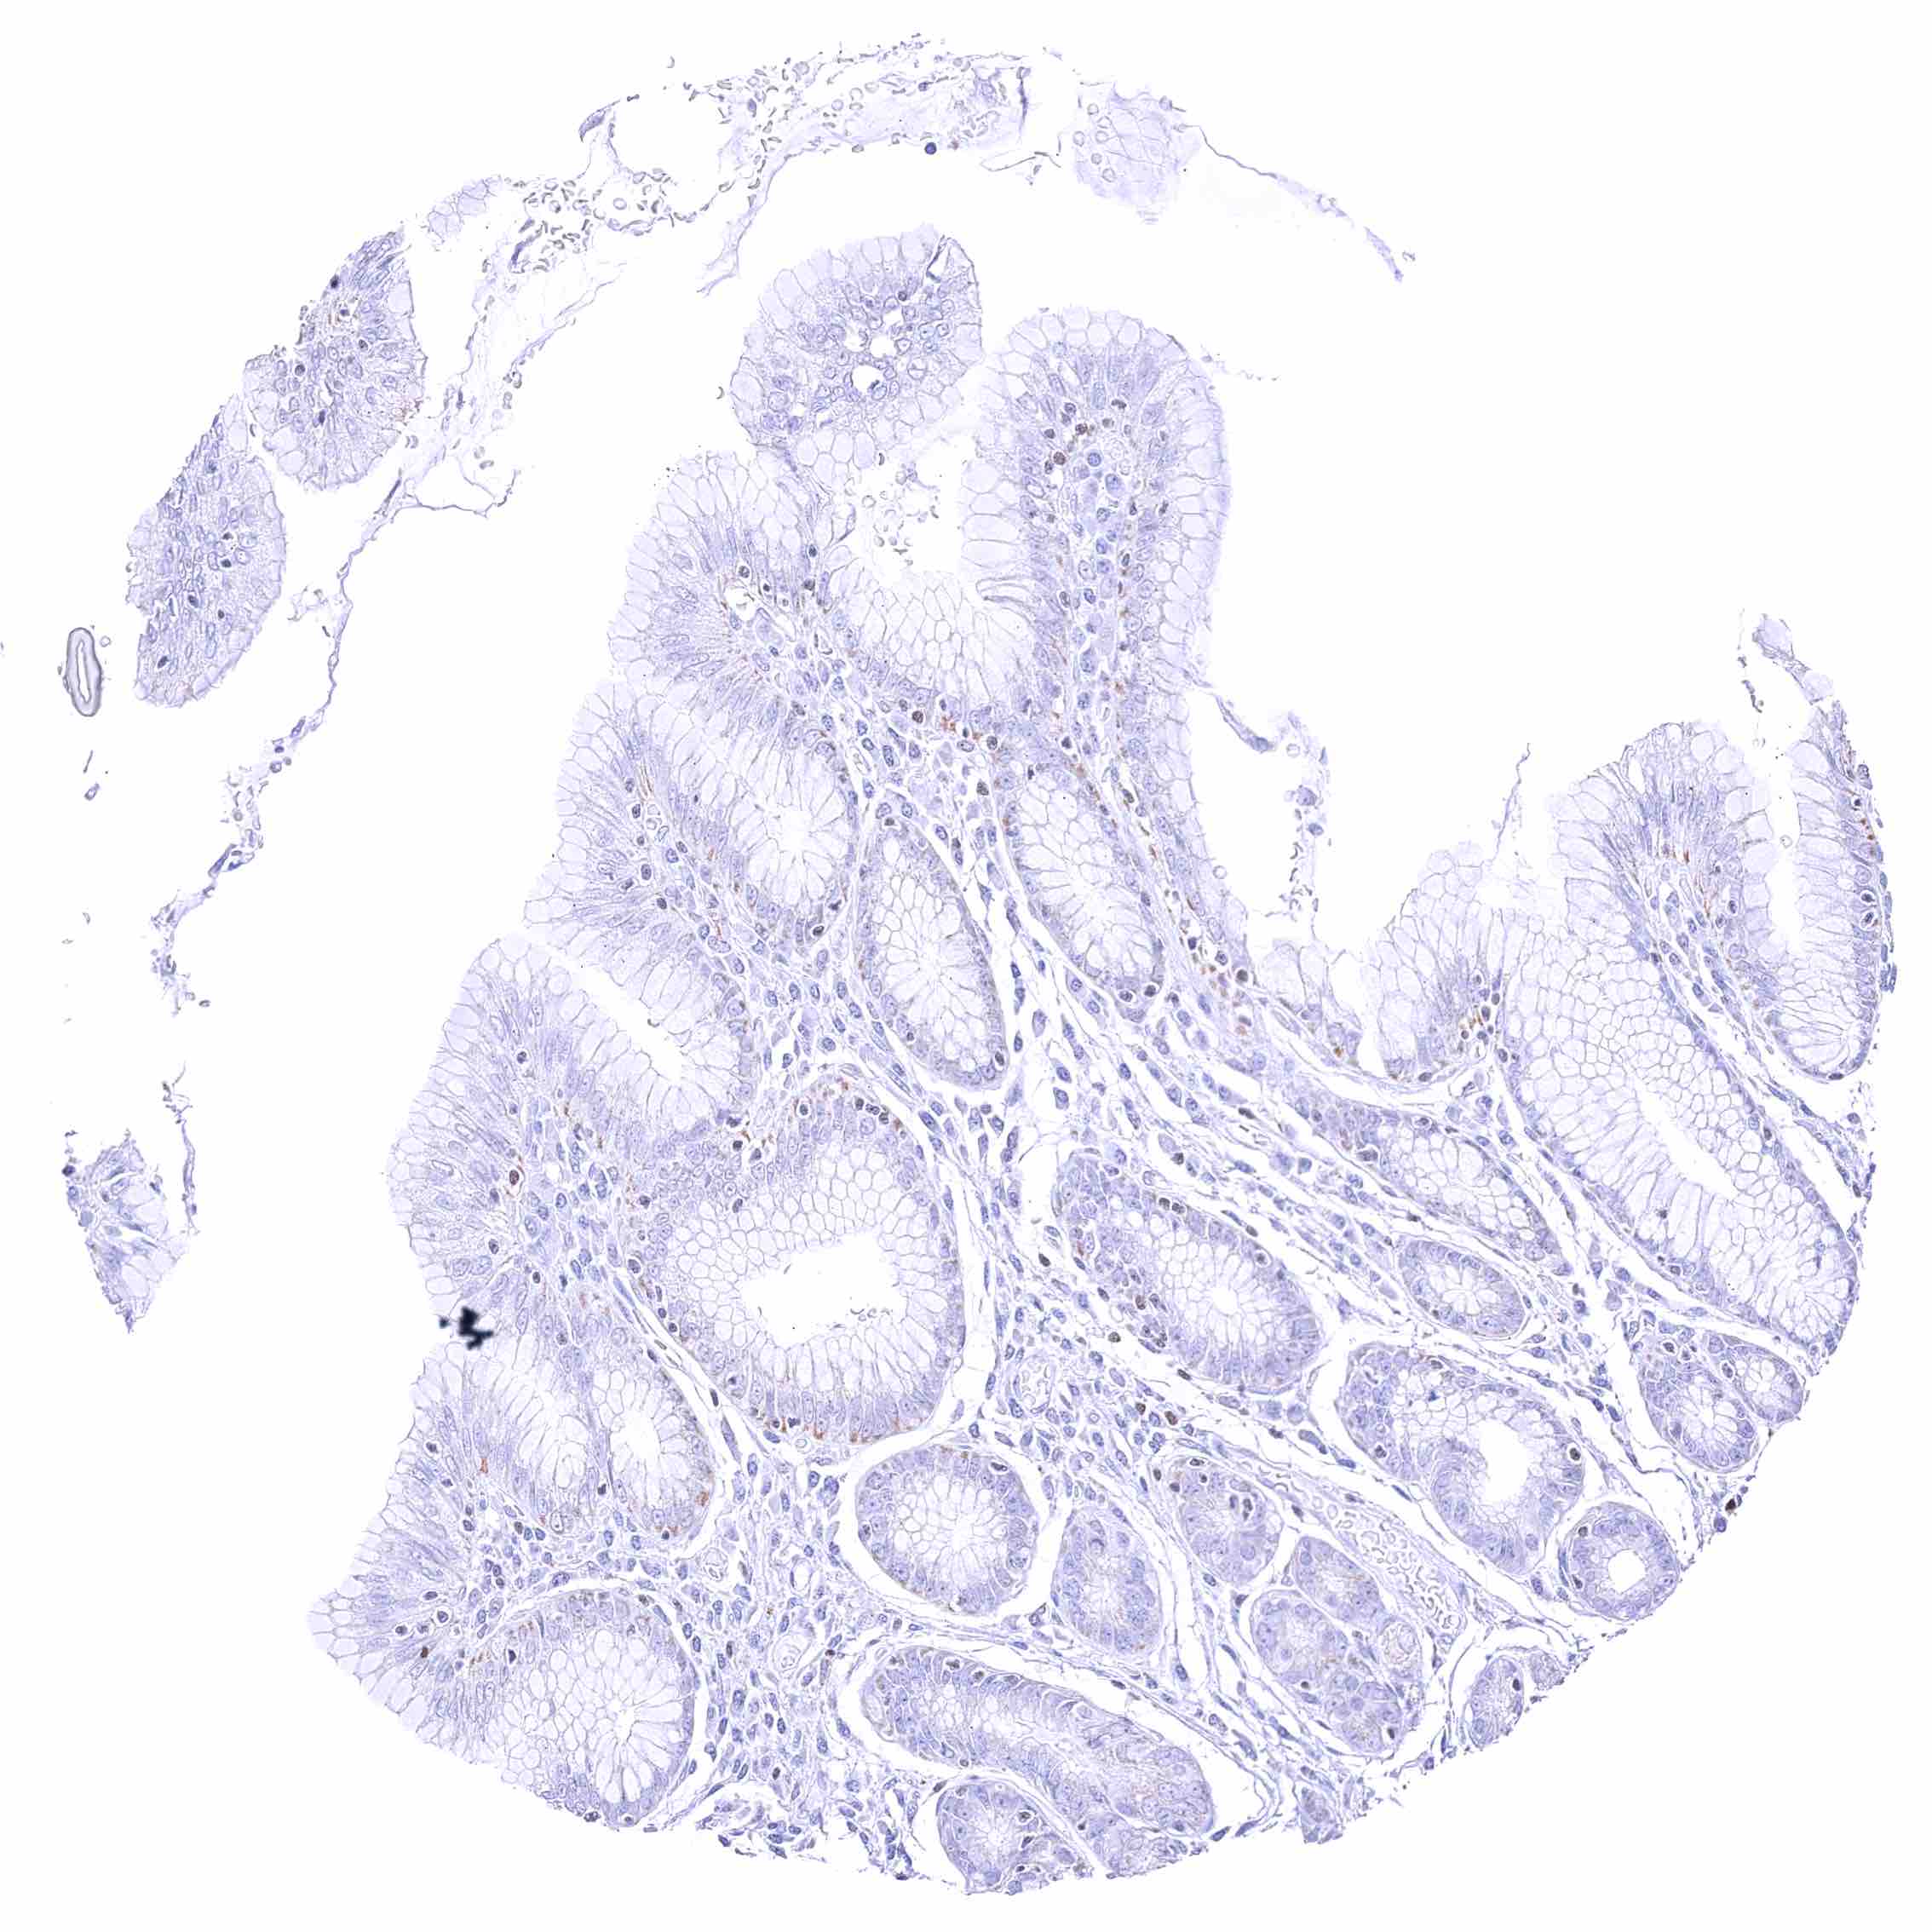

Rectum, mucosa – Nuclear GATA3 positivity of many lymphocytes.

Rectum, mucosa – Nuclear GATA3 positivity of some lymphocytes. Granular cytoplasmic GATA3 staining of epithelial cells.